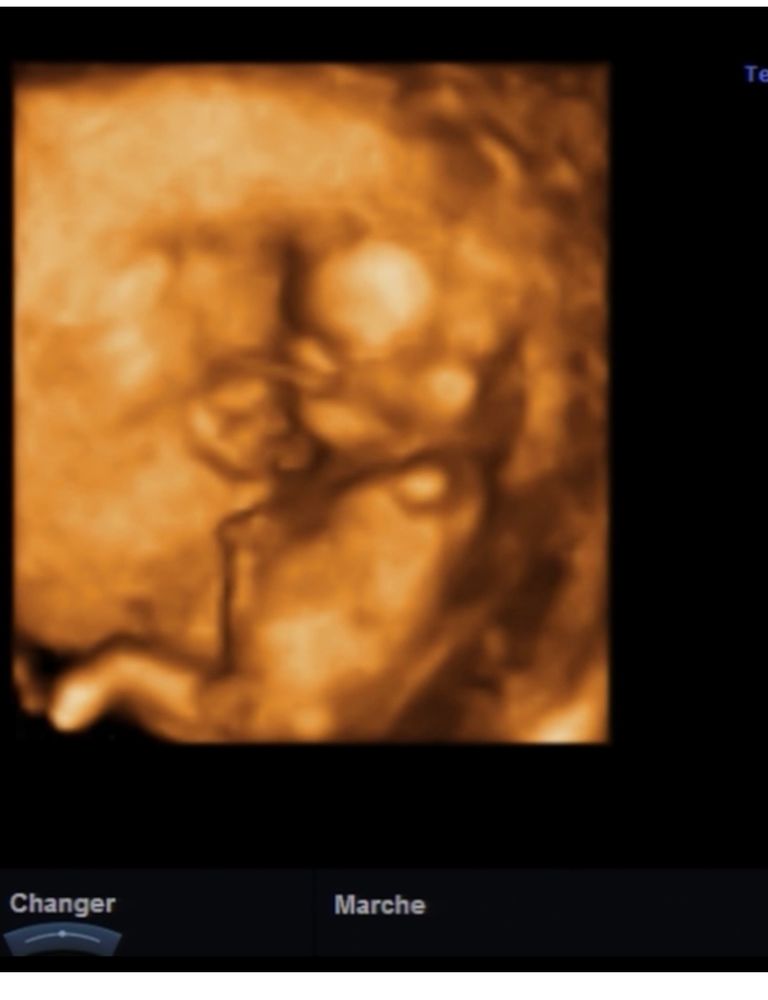

Половой бугорок в 12,3 недели

На первом фото непонятно, что именно это за отросток, часть пуповины, возможно. На втором фото половой бугорок видно четко (палочка ниже пуповины , пуповина из живота идёт) и угол наклона девчачий, мне кажется.

Скорее всего половой бугорок увидел УЗИст и озвучил это. 98 % мальчик. На таком сроке у девочек там "половые валики".